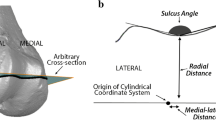

The ‘sulcus angle’ of each profile was calculated from the coordinates of the trochlear groove and those of the highest points of the medial and lateral facets (Fig. 3). The coordinates of the trochlear grooves were used to calculate a linear regression (using the method of least squares) in the frontal plane, and the trochlear groove orientation was calculated from the cosine of its gradient (Fig. 4). Furthermore, it was possible to apply virtual rotations to the trochlear profiles, to perceive the effect of externally rotating the femoral component about the intramedullary femoral axis, as applied in the surgical setting. The resulting lateral translation and minor posterior translation of the trochlear groove and facets was noted for external rotation up to 6° of about the geometric centre of the implant (Fig. 5).

Example of a two-dimensional trochlear profile at 30° of flexion (specimen #6), plotted in absolute coordinates (mm). The dashed vertical lines indicate the lateral and medial margins of the implant, and the letters indicate points of inflexion of the trochlear profile: A medial extremity B peak of medial facet C sulcus trough D peak of lateral facet E lateral extremity. The sulcus angle is ∠BCD, the height of the lateral facet is the z-coordinate difference between points C and D, and the trochlear groove is the x-coordinate of point C

The effect of applying 6° of external rotation about the geometric centre of the implant (C). The trochlear groove and lateral facet are translated proportionally to the rotation angle (θ) and radius (H). The following approximations apply for small angles (<10°) of external rotation. Lateral translation = H(sin θ); posterior translation = H(1 − cos θ)